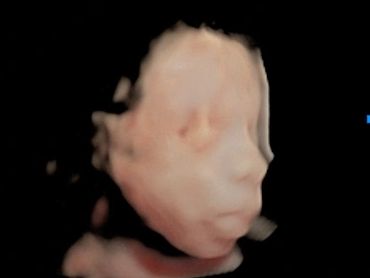

Look at these beautiful face pictures, even with an Anterior Placenta!

26 Weeks 5 Days Pregnant

26 Weeks 6 Days Pregnant